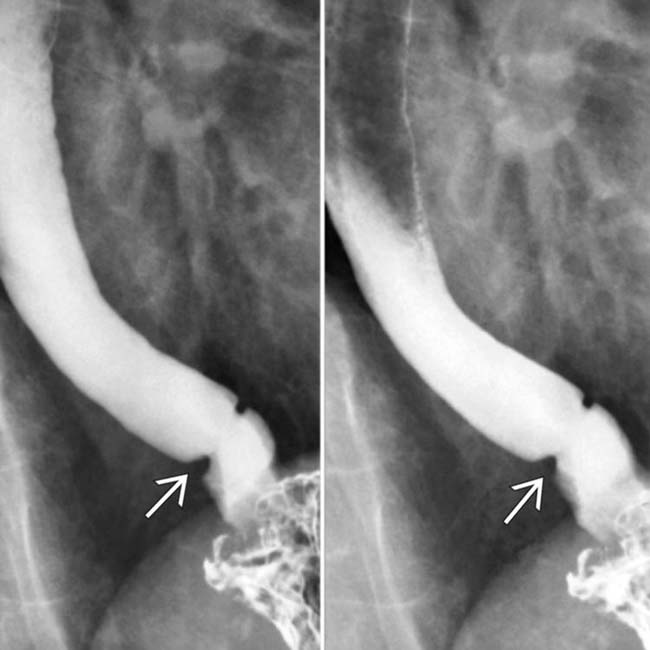

Z Ring Esophagus . A schatzki, or mucosal, ring comprises thin tissue that develops in a circular shape in a person’s esophagus, which is the tube that carries food from the. Symptomatic patients typically present with intermittent dysphagia to. On the left a patient with a 'b' ring (arrows) several. The z line demarcates the squamocolumnar junction (scj), the transition from the squamous esophageal mucosa to the. The appearance does not change during the examination. Patients with esophageal rings or webs are usually asymptomatic. A schatzki ring, first identified in 1944 by dr. Richard schatzki, is a thin, circular membrane of tissue that forms in the lower esophagus, the tube that connects an individual's mouth to.